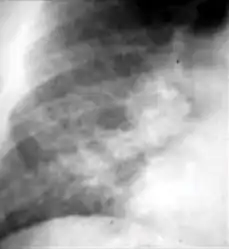

-

Chest x-ray showing nodule with margins that are indistinct or poorly defined (tree-in-bud sign) in post-primary pulmonary TB.